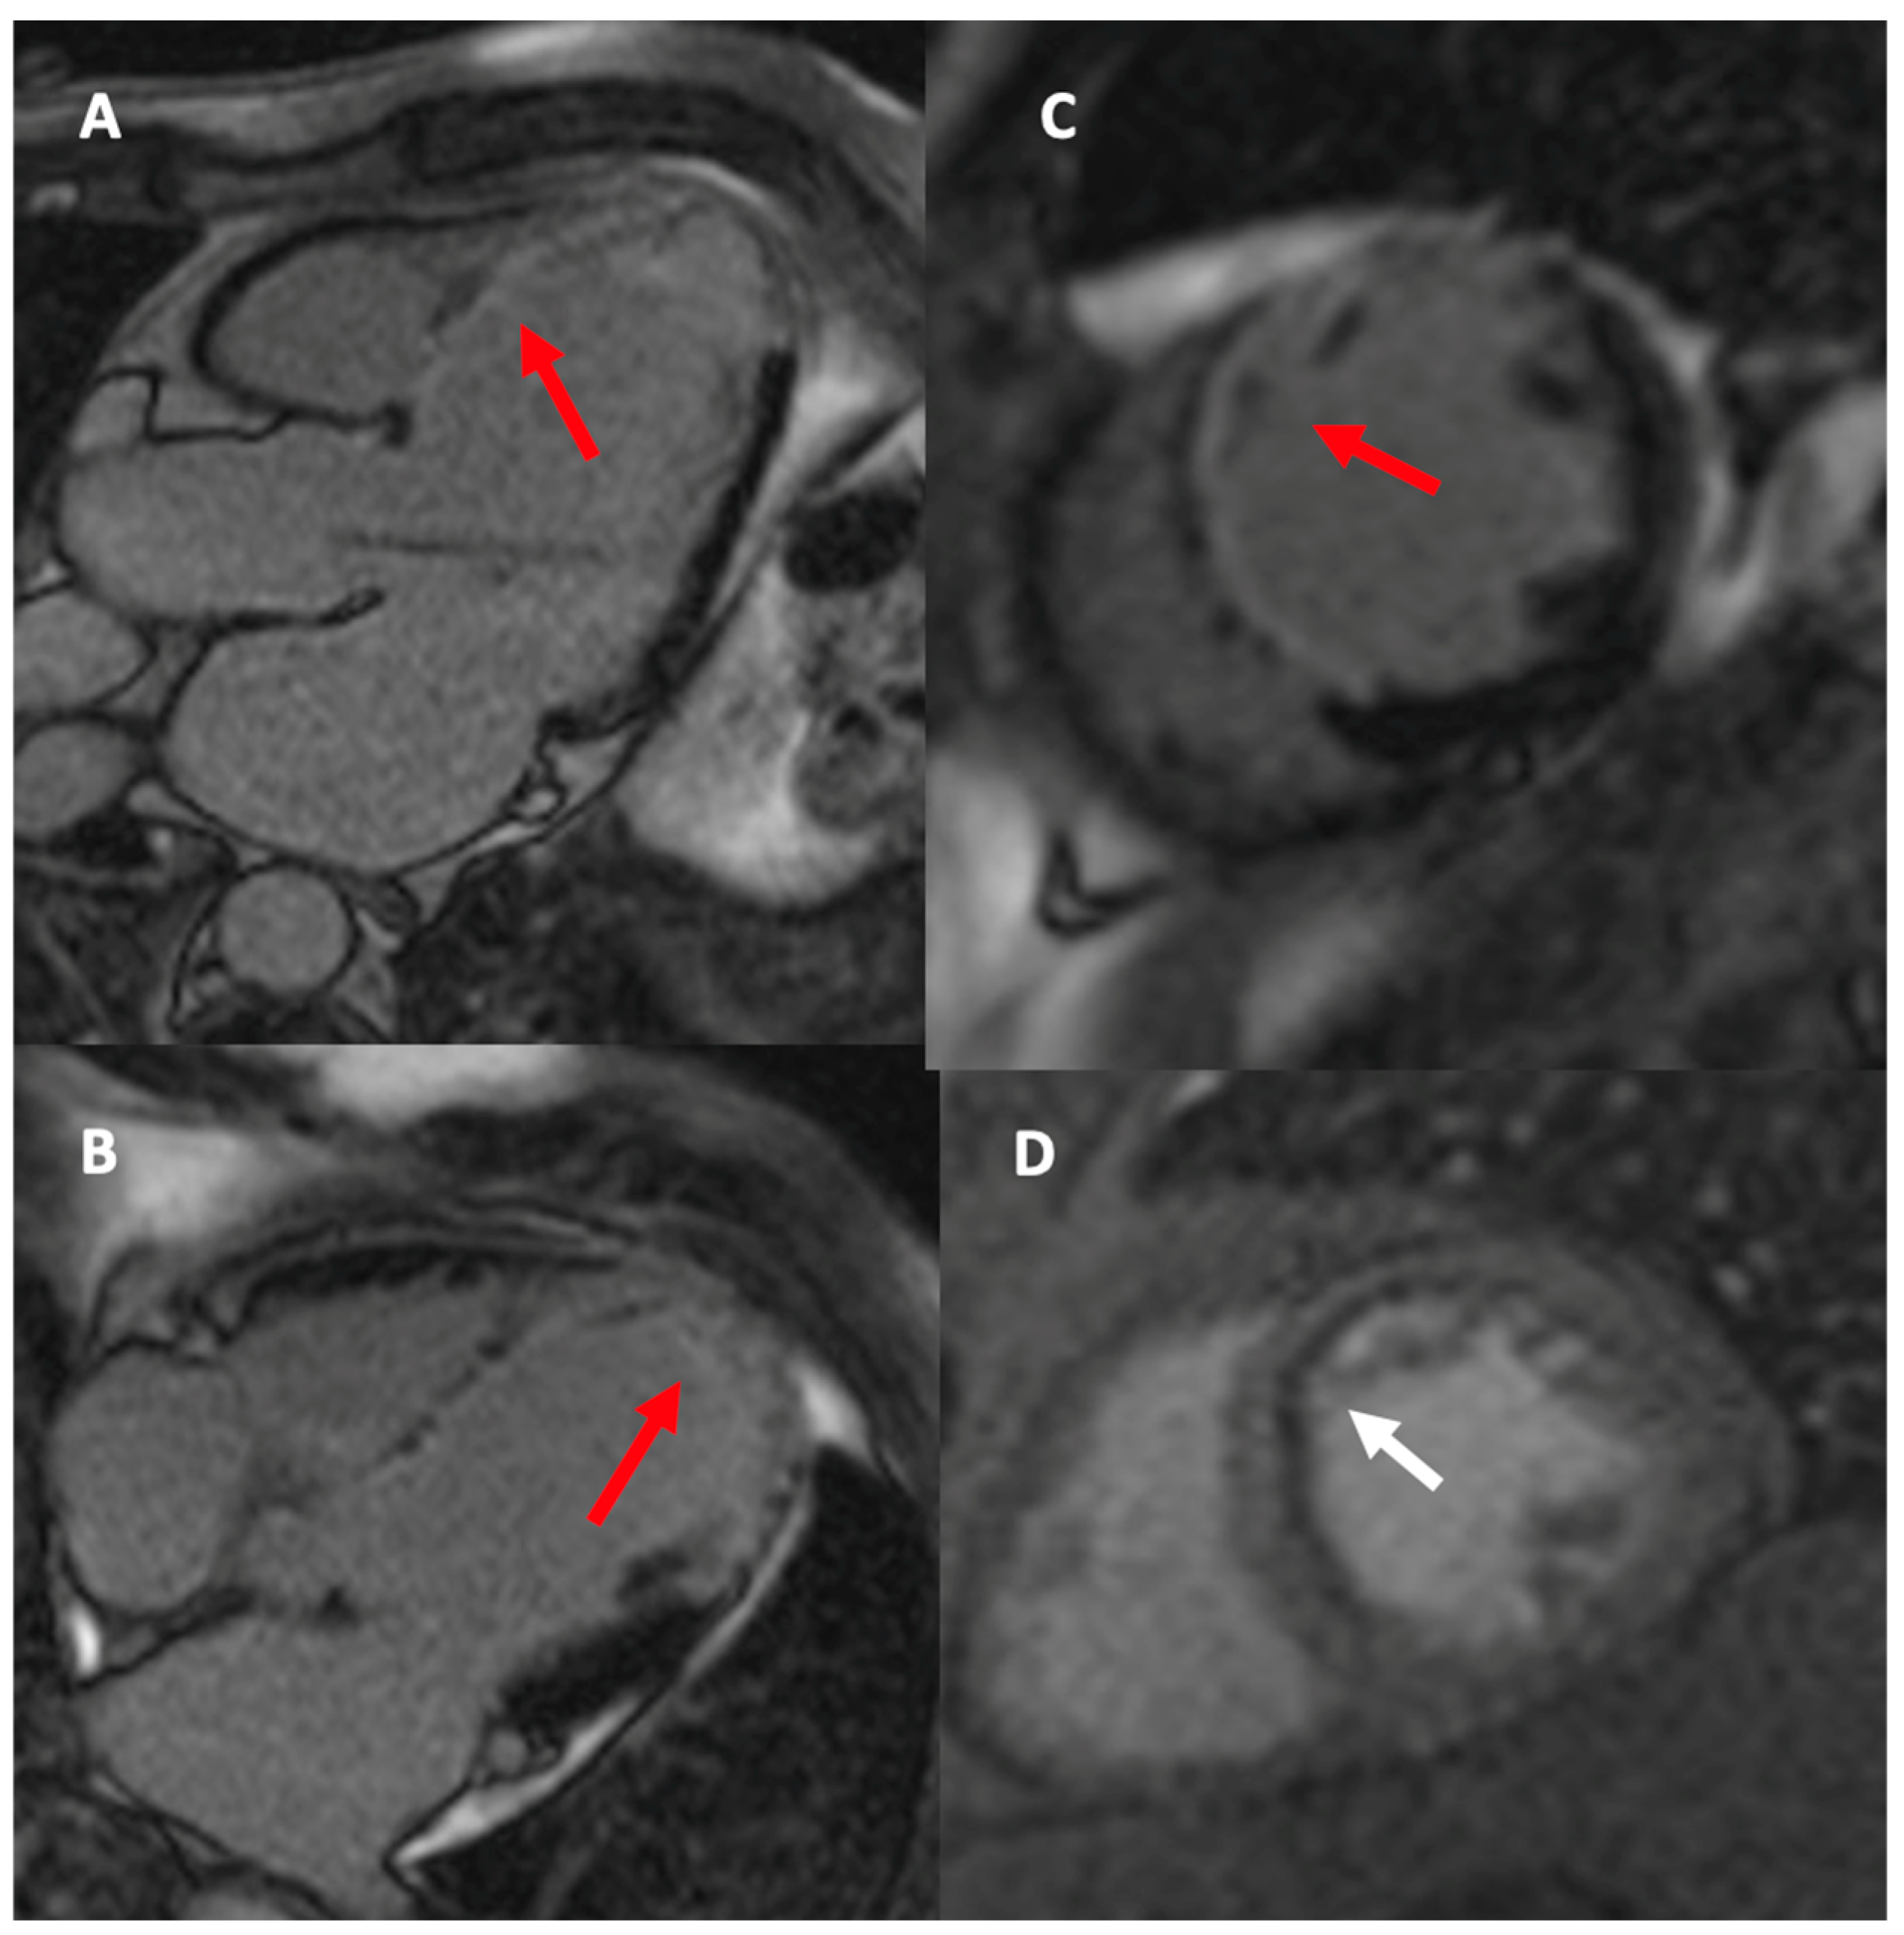

- Pegg, T.J.; Selvanayagam, J.B.; Francis, J.M.; Karamitsos, T.D.; Maunsell, Z.; Neubauer, S.; Taggart, D.P. A randomized trial of on-pump beating heart and conventional cardioplegic arrest in CABG patients with impaired ventricular function using CMR. Circulation 2008, 118, 2130–2138. [Google Scholar] [CrossRef] [PubMed]

- Thielmann, M.; Hunold, P.; Böhm, C.; Massoudy, P.; Jakob, H. Magnetic resonance imaging in CABG—Improvement of global and segmental function in patients with severely compromised LV function. Vasc. Health Risk Manag. 2007, 3, 763–768. [Google Scholar]

- Zhao, Y.; Fu, W.; Hou, X.; Zhang, J.; Biekan, J.; Zhang, H.; Wang, H.; Dong, R. Myocardial infarct size for predicting improvements in cardiac function in ICM patients after CABG. Quant. Imaging Med. Surg. 2023, 13, 7814–7827. [Google Scholar] [CrossRef]

- Zhuang, B.; Li, S.; Wang, H.; Chen, W.; Ren, Y.; Zhang, H.; Sun, Z.; Xu, L. Incremental prognostic value of CMR in patients with severe LV dysfunction undergoing CABG. Int. J. Cardiovasc. Imaging 2024, 40, 2057–2068. [Google Scholar] [CrossRef]